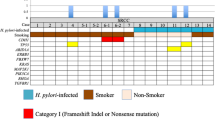

Tumor cells were dissected by laser microdissection to increase the tumor cell content because the intramucosal DGCs were small (median 6.5 mm; range 3–14 mm) and their tumor cells were scattered around the necks of glands. Small tumors with low densities of signet ring cells did not yield adequate amounts of DNA to perform WES. Accordingly, WES was performed for only nine intramucosal DGCs (Table 2). The median amount of extracted DNA was 67 ng (range 10–309 ng). A total of 239 mutations (median 20 mutations/exome; range 10–66) were found (Table S2). The most recurrently mutated gene was CDH1; CDH1 mutations were found in six of nine intramucosal DGCs (67%) and were considered as positively selected by dN/dS analysis (q < 0.001). All six cases with CDH1 mutations had ‘pure’ SRCCs, which were near the gastric angle. For the other genes, dN/dS analysis showed no significant results (q > 0.05). However, a search for 69 previously reported driver genes revealed mutations in three genes, RNF43, TGFBR2, and FAT4 (Fig. 3a, Tables S1–S3). All nine cases of Hp-uninfected intramucosal DGC had two or fewer driver mutations.

Mutational landscape and CDH1 mutation sites. a Mutational landscape of Hp-uninfected nine intramucosal DGCs and two advanced DGCs. Tumor invasion depth, location, histological type, and E-cadherin immunoreactivity are indicated. LOH loss of heterozygosity. b CDH1 mutation sites. Alterations in our sequenced tumor samples are plotted above the CDH1 protein. Somatic mutations in sporadic DGCs that have been repeatedly reported in previous studies are plotted below the CDH1 protein [Refs. 20, 21, 24, 33]. Sig signal peptide, Precursor precursor sequence, EC extracellular domain, TM transmembrane domain, Cytoplasmic cytoplasmic domain. # reported as a germline mutation of HDGC

CDH1 mutation is generally known as a loss-of-function mutation [30]. A missense mutation at L581R and loss of heterozygosity were found in Case 2 (Fig. 3a). A missense mutation at L581 was previously reported in a sporadic DGC [20]. Two-hit CDH1 mutations, including truncating mutations, were observed in Cases 5 and 6 (Fig. 3a). Cases 3 and 5 harbored a mutation at I250 (L249_T253del, I250N, respectively), which was reported as a mutation hotspot in sporadic DGCs and resulted in impaired cellular aggregation in vitro [21] (Fig. 3b). Hotspot splice site mutations (c.531 + 2 T > A, c.687 + 1_687 + 4del) reported in sporadic DGCs were observed in Cases 4 and 7 [21, 24] (Fig. 3b). These splice site mutations are thought to induce exon truncations in extracellular domain 1 to prevent the homodimerization of E-cadherin according to computer models [21]. Case 13, the only case with PDA and SRCC located at the cardia, did not harbor CDH1 mutations. Among the three cases without CDH1 mutations, we detected a frameshift RNF43 mutation (A146fs) in Case 10, but we detected no driver mutations in Cases 12 and 13. We also searched for germline mutations in CDH1, CTNNA1, PALB2, BRCA1, and RAD51C, all of which had been reported as causative genes of HDGC using blood DNA [19, 31, 32]. None of the nine subjects possessed pathogenic germline mutations in these genes. These results indicate that somatic CDH1 mutations can be considered as an early event in intramucosal SRCC carcinogenesis. E-cadherin expression was immunohistochemically reduced in all eight cases with intramucosal ‘pure’ SRCCs near the gastric angle but was maintained in DGC without CDH1 mutations at the gastric cardia (Fig. 1a, b). These data suggest that reduced E-cadherin expression contributes to SRCC development near the gastric angle, whereas the one case of PDA/SRCC at the gastric cardia may have been caused by different mechanisms.

Analysis of advanced DGCs

Genomic DNA extracted from laser capture microdissected SRCC cells in the mucosal part of two advanced DGCs was subjected to WES. For technical reasons, some PDA cells were included. A TP53 missense mutation at R248W and loss of heterozygosity was found in Case 11 (Fig. 3a, Table S4). Four driver mutations in CDH1, TGFBR2, ARID1A, and RHOA were found in Case 14 (Fig. 3a, Tables S3, S4). The CDH1 mutation at D402V has been reported in sporadic DGCs [20, 33] (Fig. 3b). Neither of the two cases had pathogenic germline mutations in the HDGC-causative genes described above.

To explore the differences in gene alternations between Hp-uninfected intramucosal and advanced DGCs, we examined nine intramucosal DGCs and 60 advanced DGCs, including two from our cohort and 58 from external datasets (Table S5). CDH1 mutations were more frequent in intramucosal DGCs (6 of 9, 67%) than in advanced DGCs (16 of 60, 27%) (p = 0.02, q = 0.11, Fig. 4a). In contrast, TP53 mutations were significantly more frequent in advanced DGCs (31 of 60, 52%) than in intramucosal DGCs (0 of 9, 0%) (p < 0.01, q = 0.03). CDH1 and TP53 co-mutated DGC occurred in only 10% (6 of 60) of advanced DGC (Fig. 4b). CDH1-mutated/TP53 wild-type advanced DGC accounted for 17% (10 of 60) and TP53-mutated/CDH1 wild-type advanced DGC accounted for 42% (25 of 60) of total advanced DGCs. The difference of CDH1 and TP53 mutation frequencies between intramucosal and advanced DGCs suggests that Hp-uninfected advanced DGCs may be more likely develop from precursor lesions other than CDH1-mutated intramucosal DGCs.

Driver gene mutation frequencies in Hp-uninfected intramucosal and advanced DGCs. a Comparison of mutation frequencies in driver genes between Hp-uninfected intramucosal DGCs (n = 9) and advanced DGCs (n = 60). p and q values were provided for CDH1 and TP53 calculated by two-tailed Fisher’s exact test with Benjamini–Hochberg adjustment. There were no significant differences in other genes. b Detailed CDH1/TP53 mutation profiles for Hp-uninfected intramucosal and advanced DGCs